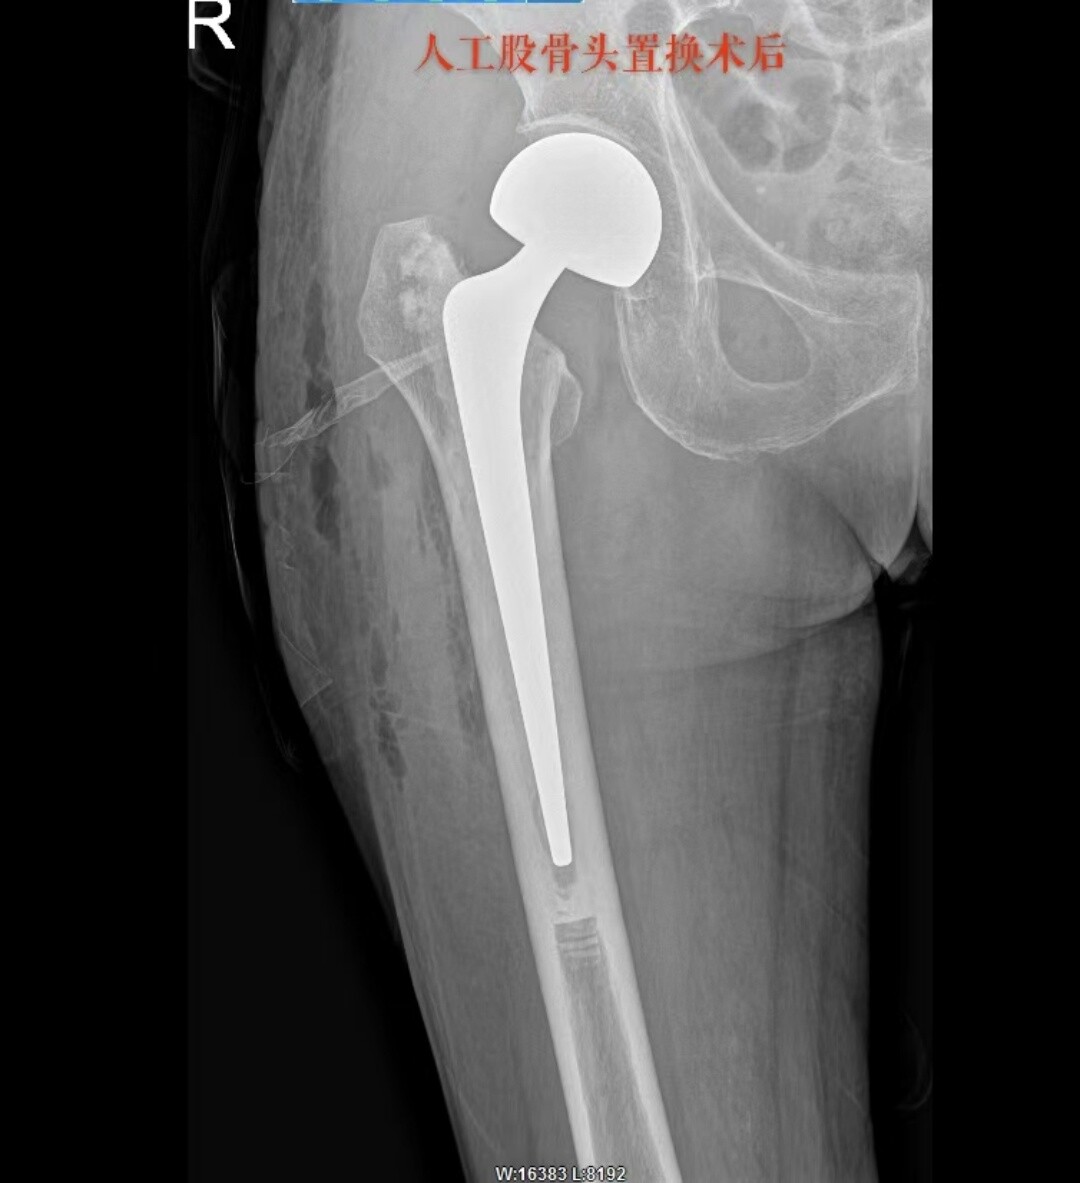

81 岁患者的朱奶奶,因摔伤致右髋部疼痛 2 天入院,确诊为右侧股骨颈骨折。永兴县人民医院骨二科团队在充分评估朱奶奶的病情后,决定采用 “保留梨状肌人工股骨头置换术”,术后第一天,朱奶奶便在医护人员的保护下顺利下地站立并行走,疼痛感明显减轻,关节活动功能恢复良好。